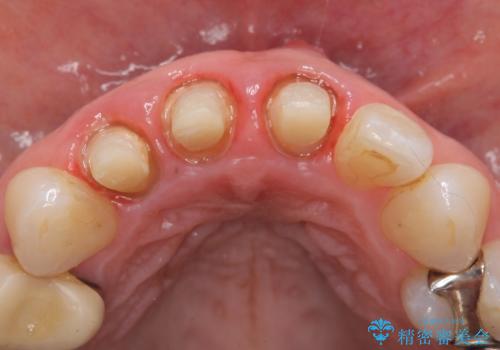

- 前歯の長さが違うのが気になるといらっしゃった方の症例です。

根尖病変を認めたため再根管治療を行った後、オールセラミッククラウン(スペシャル)にて補綴を行いました。

- オールセラミッククラウン(スペシャル)…¥130,000×3、仮歯…¥10,000×3、ファイバーコア…¥20,000×3費用は治療当時の料金となります